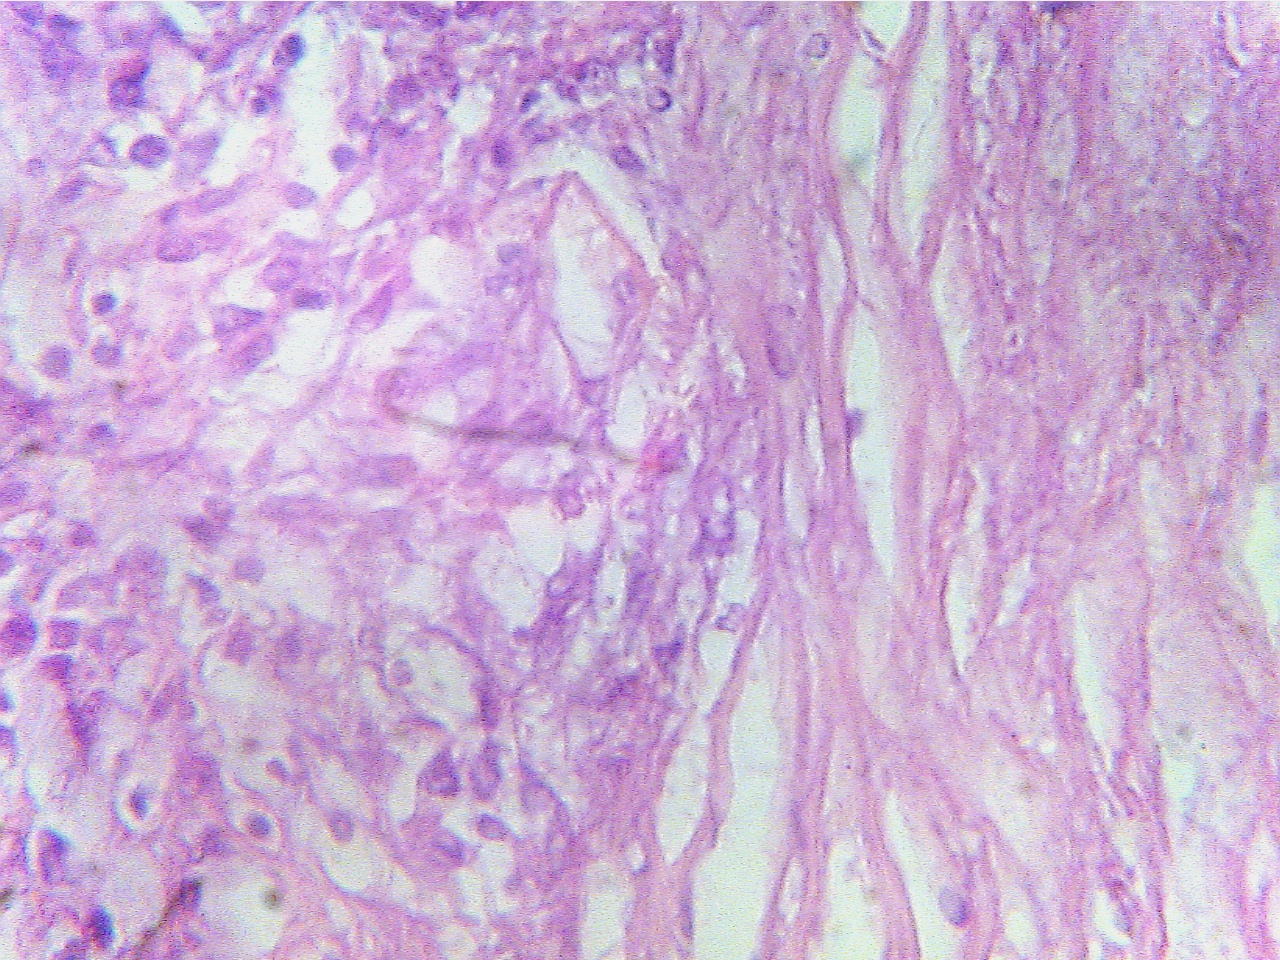

Ghon tubercle (400X2.0)

Macrophages (left), fibrous capsule

(center), necrotic Macrophages

(round dark blue at left), fibrous capsule

region

(right)

Ghon tubercle (400X2.8)

Ghon

tubercle (400X2.8)

Macrophages (round dark blue at left), fibrous

capsule Central amorphous

acellular necrotic region